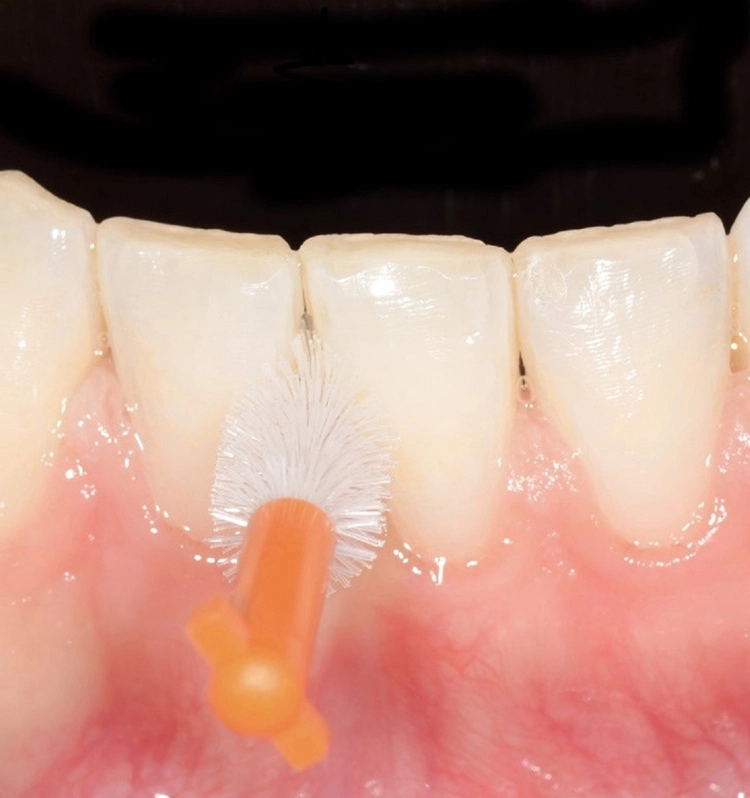

Die derzeit höchste Evidenz für eine Reduktion von Plaque und Gingivitis weisen Interdentalraumbürsten auf [18-24]. Diese sind daher auch in den neuen S3-Leitlinien der Deutschen Gesellschaft für Parodontologie als bevorzugtes Mittel zur Interdentalraumhygiene aufgeführt [12]. Der Empfehlung zufolge sollte die passende Auswahl vom zahnmedizinischen Fachpersonal getroffen werden und sich nach den anatomischen Gegebenheiten des jeweiligen Interdentalraums richten. Zu den Fragen, wie genau diese Auswahl zu treffen ist, welche Formen oder Bürstenanordnungen zu bevorzugen sind oder mit welcher Kraft die Interdentalraumbürste in den Zahnzwischenraum eingeführt werden sollte, besteht bislang jedoch noch kein wissenschaftlich eindeutig begründeter Konsensus [25].

In der Praxis werden an Patienten zuweilen mit Messsonden diverse Größen ausprobiert, um eine entsprechende Empfehlung abzugeben [26]. Allerdings ist ihr Wert umstritten. Eine korrekt angepasste Interdentalraumbürste sollte den kompletten Interdentalraum reinigen und mit „mittlerem“ Druck ein- und auszuführen sein. Wenn sie zu dünn ist, hat sie eine zu geringe Reinigungswirkung; ist sie hingegen zu dick, besteht Traumatisierungsgefahr. Abbildung 2 zeigt die Einprobe und Auswahl am Beispiel des Interdentalraums 41/42.